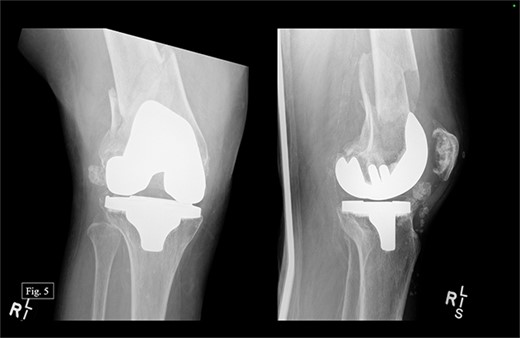

The patient presented to our level 1 trauma center in September 2022 with acute right knee pain and unable to ambulate. She was seen and evaluated in the emergency department, where she was found to have evidence of a right distal periprosthetic femur fracture (Su Type II) after a ground-level fall (Fig. 5). Because of the open box configuration of the native TKA implant and adequate available bone stock, a standard Stryker right retrograde intramedullary nail (IMN) was selected.